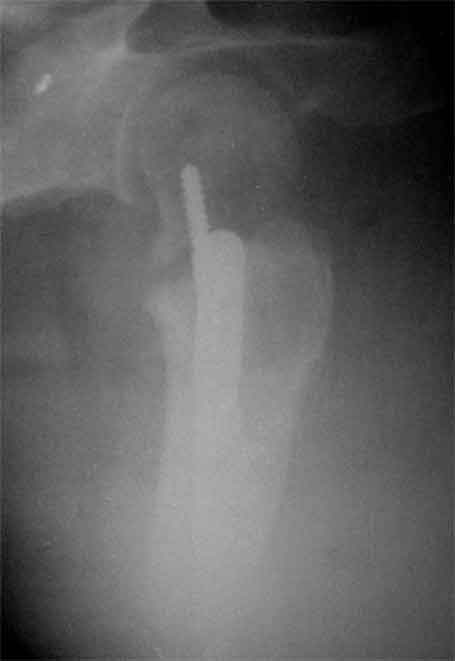

Доброго время суток, коллеги. Обратилась на консультацию пациентка 52 лет. травма и первичный остеосинтез перелома бедра около года назад, далее был обнаружен перелом шейки бедра (возможно ятрогенный), реостеосинтез реконструкционным гвоздем 8 месяцев назад. Конченость не опорна. В больнице, где выполнялись эти вмешательства предложили выполнить THR с длинной ножкой. Возможно ли в такой ситуации добиться сращения шейки при помощи каких-либо остеотомий?

На мой взгляд дистальный перелом срощен, а состояние тазобедренного сустава и молодой возраст пациентки позволяют произвести вальгизирующую остеотомию проксимального бедра. В случае, если нет сращения дистального перелома можно фиксировать длинным DHS; Если есть сращение- обычным DHS.

Коллкега на представленных снимках имеется ротационная стабильность и плохо репонированный перелом. В данный момент думать об эндопротезтровании или межвертельной остеотомий рано, так как перелом диафиза бера еще полностью не сросся, я думаю, надо на данном этапе попытаться стабилизировать перелом шейки бедра конюлированными винтами, удалить проксимальный винт, попытатся сделать репозицию, хотя маловероятно, что получется добиться улучшения, и стабилизировать 3 конюлированными винтами и дать компресию, таким образом дать шанс, может перелом срастется до удаления штифта. Удачи

Применение одного импланта для лечения ипсилатеральных переломов резко ограничено из-за риска осложнениий, связанных с применением неадекватной фиксации. По литературным данным, осложнения после применения зарекламированных реконструктивных гвоздей для лечения ипсилатеральных переломов доходили до 56%.

Несостоятельность фиксации шейки не давала возможности срастись перелому, потому что запланированнная динамическая нагрузка в большинстве случаев прекращалалась из-за вторичного варусного смещения шейки.

В данном случае навряд ли можно ожидать образования сращения на бедре и еще имеется укорочение засчет варуса.

поможет установит сращение на шейке и бедре. Восстановление длины можно сделать за счет вальгусной остеотомии оригинальным методом Blade Plate. На бедро шт ифт ретроградно или пластина, кому что нравится. На мой взгляд, еще имеется шанс спасти головку остеотомией.